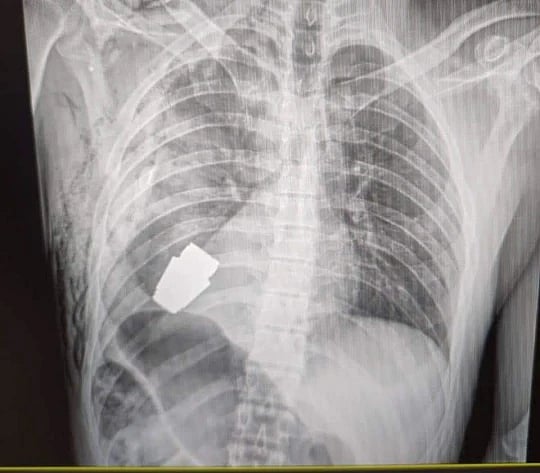

அதாவது போரின்போது உக்ரைன் இராணுவ வீரர் ஒருவரது ஒருவரின் உடலில் கையெறி குண்டு என்று சொல்லப்படும் Grenade Bomb துளைத்துக்கொண்டு வயிற்று பகுதியில் சிக்கியிருந்தது. அந்த வெடிகுண்டு வெடிக்கும் நிலையில் இருந்துள்ளது. இதனால் அதனை உடனடியாக அறுவை சிகிச்சை செய்து அகற்றவேண்டிய கட்டாயத்தில் மருத்துவர் இருந்தார்.

இந்த நிலையில் வின்னிட்சியாவைச் சேர்ந்த அறுவை சிகிச்சை நிபுணர் மேஜர் ஜெனரல் ஆண்ட்ரி வெர்பா என்பவர் இந்த அறுவை சிகிச்சையை மேற்கொள்ள முனவந்தார். தொடர்ந்து அவருக்கு அறுவை சிகிச்சை மேற்கொள்ளப்பட்டது. அப்போது அவரது உடலிலிருந்து கையெறி குண்டை வெற்றிகரமாக அகற்றினார்.

பின்னர் '30mm VOG-30' என்ற அந்த கையெறி குண்டை அருகிலிருந்த வீரர்கள் உடனடியாக செயலிழக்கச் செய்தனர். தொடர்ந்து அறுவை சிகிச்சை மேற்கொள்ளப்பட்ட இராணுவ வீரர் தொடர் சிகிச்சையில் இருந்து வருகிறார். தன் உயிரையையும் பொருட்படுத்தாமல் இராணுவ வீரரின் உயிரை காப்பாற்றிய மருத்துவரின் செயலால் பாராட்டுக்கள் குவிந்து வருகின்றன.